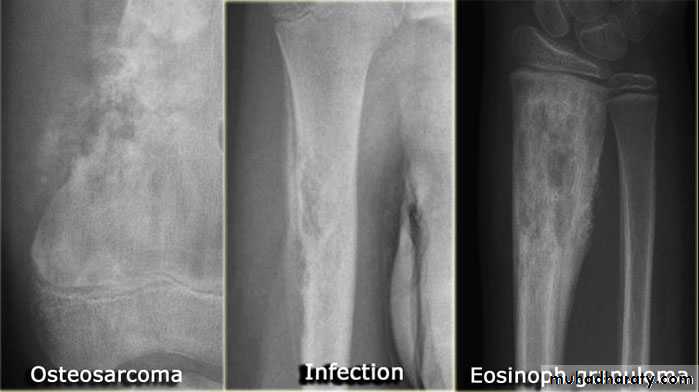

Primary malignant tumoursOsteosarcoma ( osteogenic sarcoma )

Chondrosarcoma :

Ewing sarcoma

. osteomyelitis

.Osteomyelitis.Malignant bone tumour , particularly Ewing sarcoma & osteosarcoma